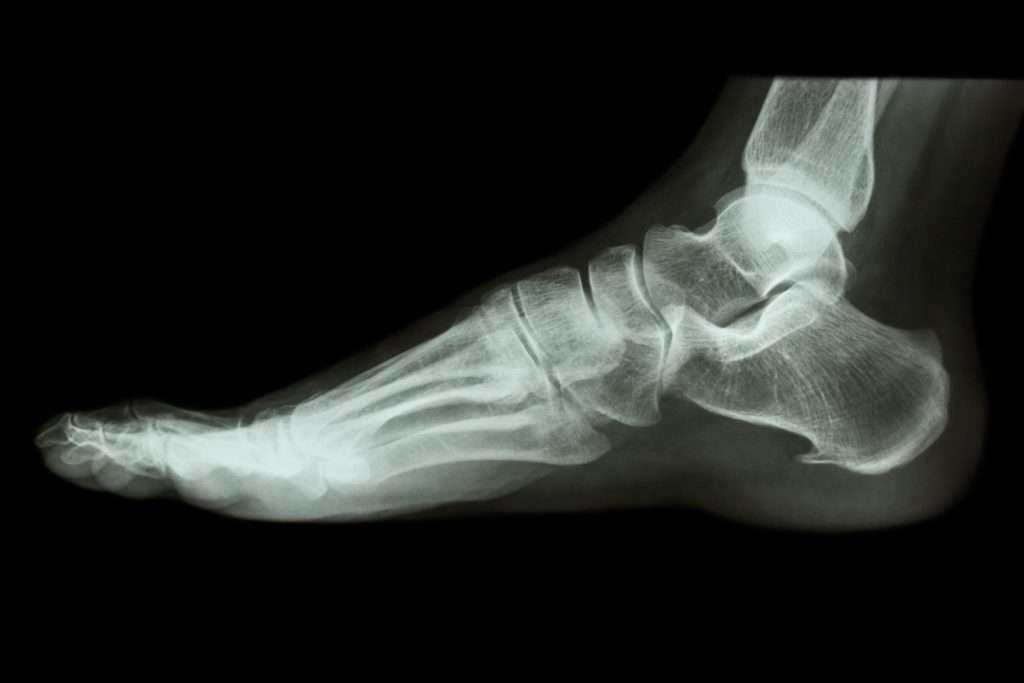

Anatomy of the foot

The feet contain 52 bones (which means 26 bones in each foot), which comprise about one quarter of all the bones in your body. Yes, little do we realize that something as "lowly" as our feet can have so much bones. However, it can give a lot of foot problems.

Each foot is a complex structure that contains ligaments, joints, tendons and muscles that allow it to move in a number of ways.